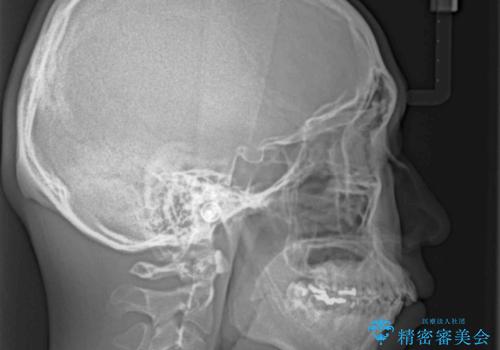

- 口元の突出感と下の前歯のがたつきを主訴として来院された患者様です。

口元の突出感と叢生改善のため上下左右の第一小臼歯4本を抜歯し、ワイヤー装置にて矯正治療を行うこととしました。

左上はアンカースクリューを併用することでスムーズに抜歯スペースを閉じることができました。